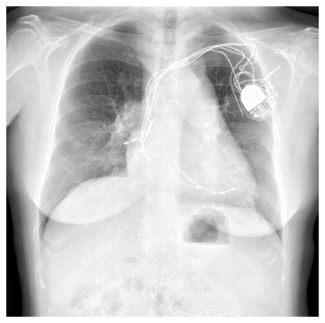

Coronary and graft angiography was performed via left transradial approach. Native coronary angiography revealed left coronary dominance with significant obstruction of the left main coronary artery by a single discrete lesion. The LAD and circumflex arteries were patent but diseased, with the occluded first obtuse marginal branch being supplied by a patent saphenous vein graft. Notably, competitive flow was present in the mid-LAD due to filling from both the proximal native vessel and LIMA graft (Figure 1, Video 1).

Coronary and graft angiography was performed via left transradial approach. Native coronary angiography revealed left coronary dominance with significant obstruction of the left main coronary artery by a single discrete lesion. The LAD and circumflex arteries were patent but diseased, with the occluded first obtuse marginal branch being supplied by a patent saphenous vein graft. Notably, competitive flow was present in the mid-LAD due to filling from both the proximal native vessel and LIMA graft (Figure 1, Video 1).

Based upon competitive flow noted during native vessel angiography, internal mammary graft patency was expected. Surprisingly, the LIMA was found to be proximally occluded (Figure 2). To reconcile the apparent discrepancy, exploration was performed for alternate sources of LAD filling. It was found that the LIMA downstream of the occluded origin filled via a single branch arising directly from the ipsilateral thyrocervical trunk (Figure 3, Video 2). The etiology of the proximal LIMA occlusion remains uncertain, but conceivably could have been related to vessel injury during coronary artery surgery. Regardless, an initial conservative strategy was felt appropriate, with the possibility of percutaneous intervention (native vessel or graft), or repeat CABG in the future, if required.

Based upon competitive flow noted during native vessel angiography, internal mammary graft patency was expected. Surprisingly, the LIMA was found to be proximally occluded (Figure 2). To reconcile the apparent discrepancy, exploration was performed for alternate sources of LAD filling. It was found that the LIMA downstream of the occluded origin filled via a single branch arising directly from the ipsilateral thyrocervical trunk (Figure 3, Video 2). The etiology of the proximal LIMA occlusion remains uncertain, but conceivably could have been related to vessel injury during coronary artery surgery. Regardless, an initial conservative strategy was felt appropriate, with the possibility of percutaneous intervention (native vessel or graft), or repeat CABG in the future, if required.